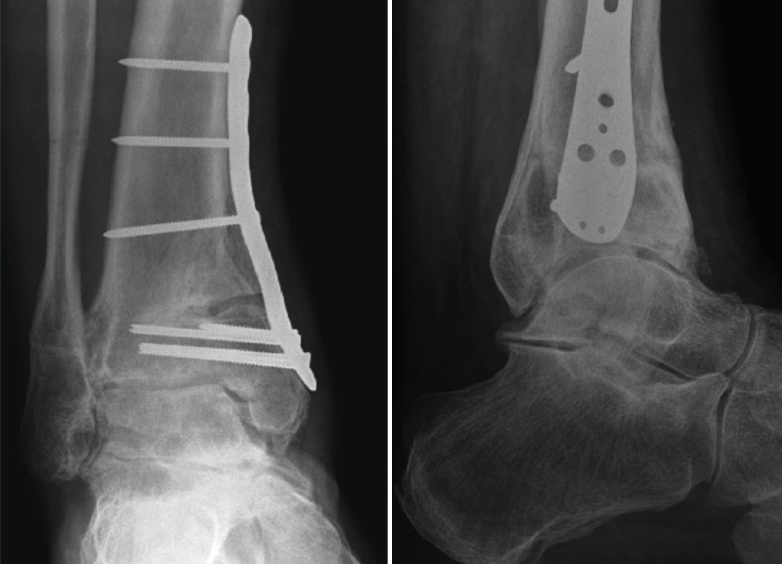

Figura 2. Resultado del caso de la Figura 1 tras osteotomía supramaleolar de adición medial fijada con placa de titanio de bajo perfil (caso del Dr. Víctor Valderrábano).

La meta de la SMOT es la reconstitución o modificación del eje del tobillo para modificar la carga articular y, de esta manera, disminuir o retrasar la progresión de la lesión al cartílago articular(15,16,17,18). Dependiendo de los grados necesarios para la corrección, la osteotomía puede ser conformada por una cuña de apertura medial (Figuras 1 y 2) o, si se requieren > 10° de corrección o una sindesmosis fusionada, una cuña de cierre lateral para evitar una discrepancia de longitud importante(19). Cualquiera que sea la técnica, suele incluirse osteotomía del peroné en ambos casos. Si el peroné tiene claramente una longitud mayor a la fisiológica, restaurar la posición neutra del astrágalo resulta imposible. Knupp et al.(20) realizaron una modificación a la clasificación de la artrosis en varo de tobillo mediante la adición de un algoritmo de tratamiento para los procedimientos extraarticulares. Esta nueva clasificación permite categorizar los distintos tipos de artrosis de tobillo en varo y facilita la decisión terapéutica, especialmente cuando una SMOT aislada resulta insuficiente. Por otra parte, se puede añadir a este procedimiento una osteotomía intraarticular (plastia de pilón tibial o plafonplastia) si se observa persistencia de la inclinación astragalina por artrosis unicompartimental (Figura 3).

Esta técnica conjunta fue descrita por Hinterman et al.(21), quienes demostraron resultados favorables tras un seguimiento de 5,9 años. Otros procedimientos adicionales en caso de deformidad del retropié o inestabilidad ligamentosa deben ser igualmente considerados(10).